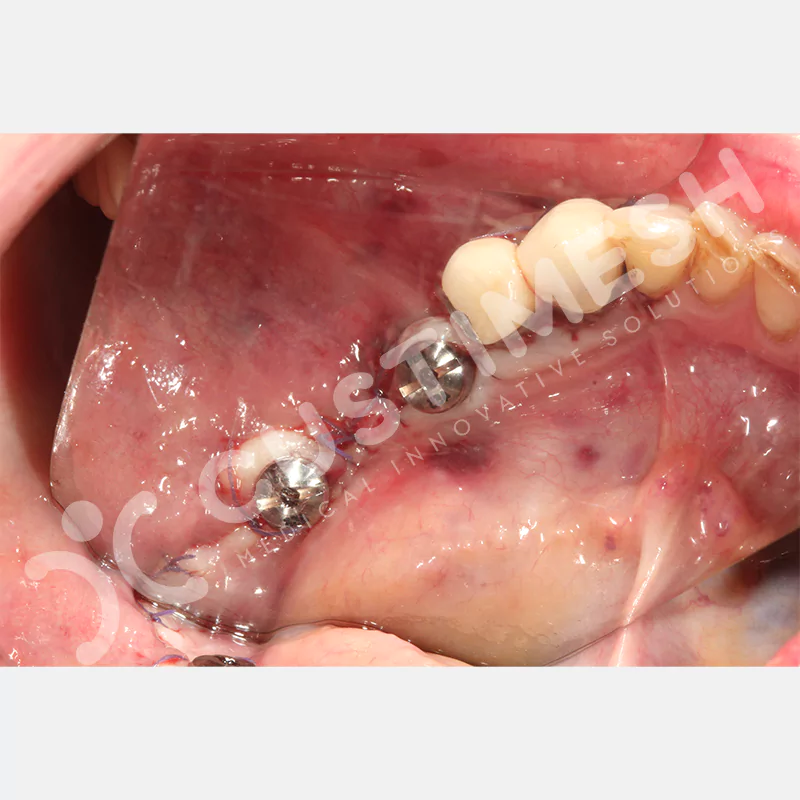

VAKA 2